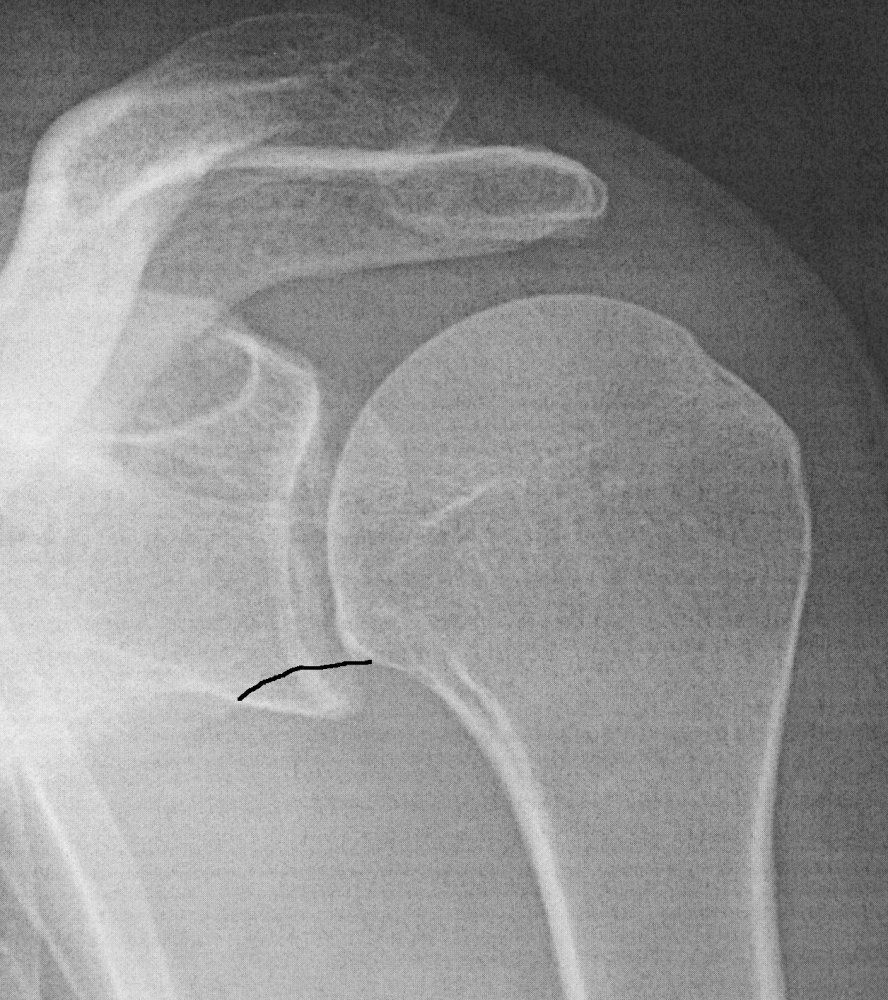

Beim mir war gestern OP Vorbesprechung mit meinem Orthopäden und Schulterchirug - er hat in der Hinsicht einen guten Ruf. Nach gründlicher Durchsicht der MRT Bilder und Röntgenbilder ist sein Fazit: Kann man operieren, muss aber nicht. Bei mir ist auch ein Stück vom Knochen ab, aber er war sich nicht mal sicher ob das vom jetzigen Unfall ist oder eine alte Verletzung. Die restlichen typischen Verletzungen sind zwar sichtbar, aber nicht besonders stark ausgeprägt. Die Hauptprobleme kommen von Trizepssehne, Bizepssehne, Brustmuskel und Kapsel.

Da die Beweglichkeit schon wieder gut ist und die Schulter auch stabil erscheint, möchte er erst mal weiter konventionell behandeln mit Physio und Stärkungsübungen - lediglich wenn die Schulter habituell auskugeln sollte oder sich bei Alltagsbewegungen verrenken sollte, würde er operieren.